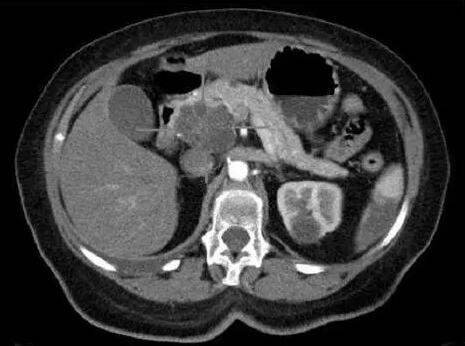

图片摘自:medicalxpress.com